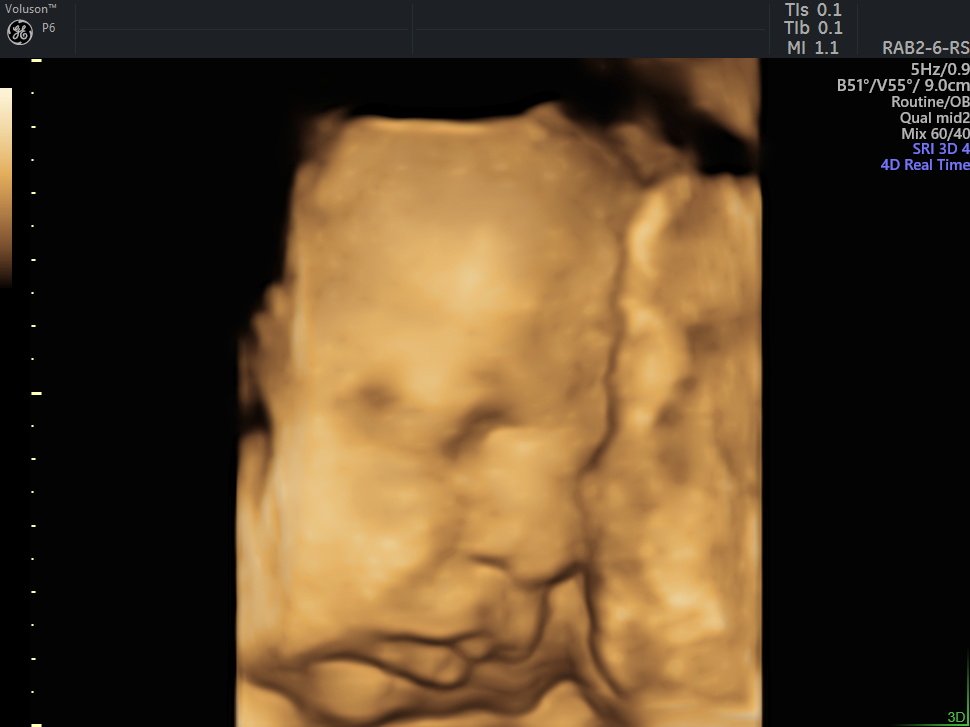

4 D Ultrasonografi

4 Boyutlu (Renkli) Ultrason ve Doppler Ultrasonografi